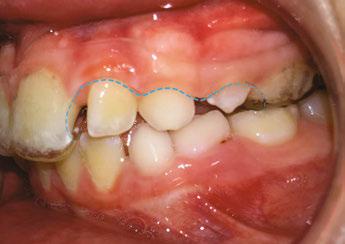

Figure 1: Early interproximal carious lesions and areas of plaque accumulation are not visually detectable in a patient with labial bracket placement. Providing these visualized images to the patient can serve as an effective tool for motivating oral hygiene practices and accurately informing them of the potential risk for dental caries development

of its key strengths lies in enhancing communication between patients and practitioners. All examination outcomes are stored as photographic images, color-mapped graphics, and quantitative data, enabling visualization of lesion changes over time — from the initiation of orthodontic treatment, through interim monitoring, to post-removal of appliances. As a result, patients are not merely given fleeting verbal explanations but are presented with objective data on the status of their teeth, which strongly motivates them toward improved oral hygiene and increases their engagement with the treatment process. The images above present Q-ray scans from patients with labial and lingual bracket attachments. Presenting such imagery to patients not only underscores the importance of oral hygiene, increasing the educational effect, but also provides objective evidence that may protect clinicians in the event of dental caries or other complications arising during orthodontic treatment.

Figure 2: In a patient with lingual bracket placement, early interproximal carious lesions and plaque accumulation are detectable on the lingual surfaces with brackets, despite the absence of visible abnormalities on the labial surfaces. This finding highlights the importance of targeted oral hygiene education for lingual orthodontic patients, emphasizing the management of visually inaccessible risk sites to prevent caries development